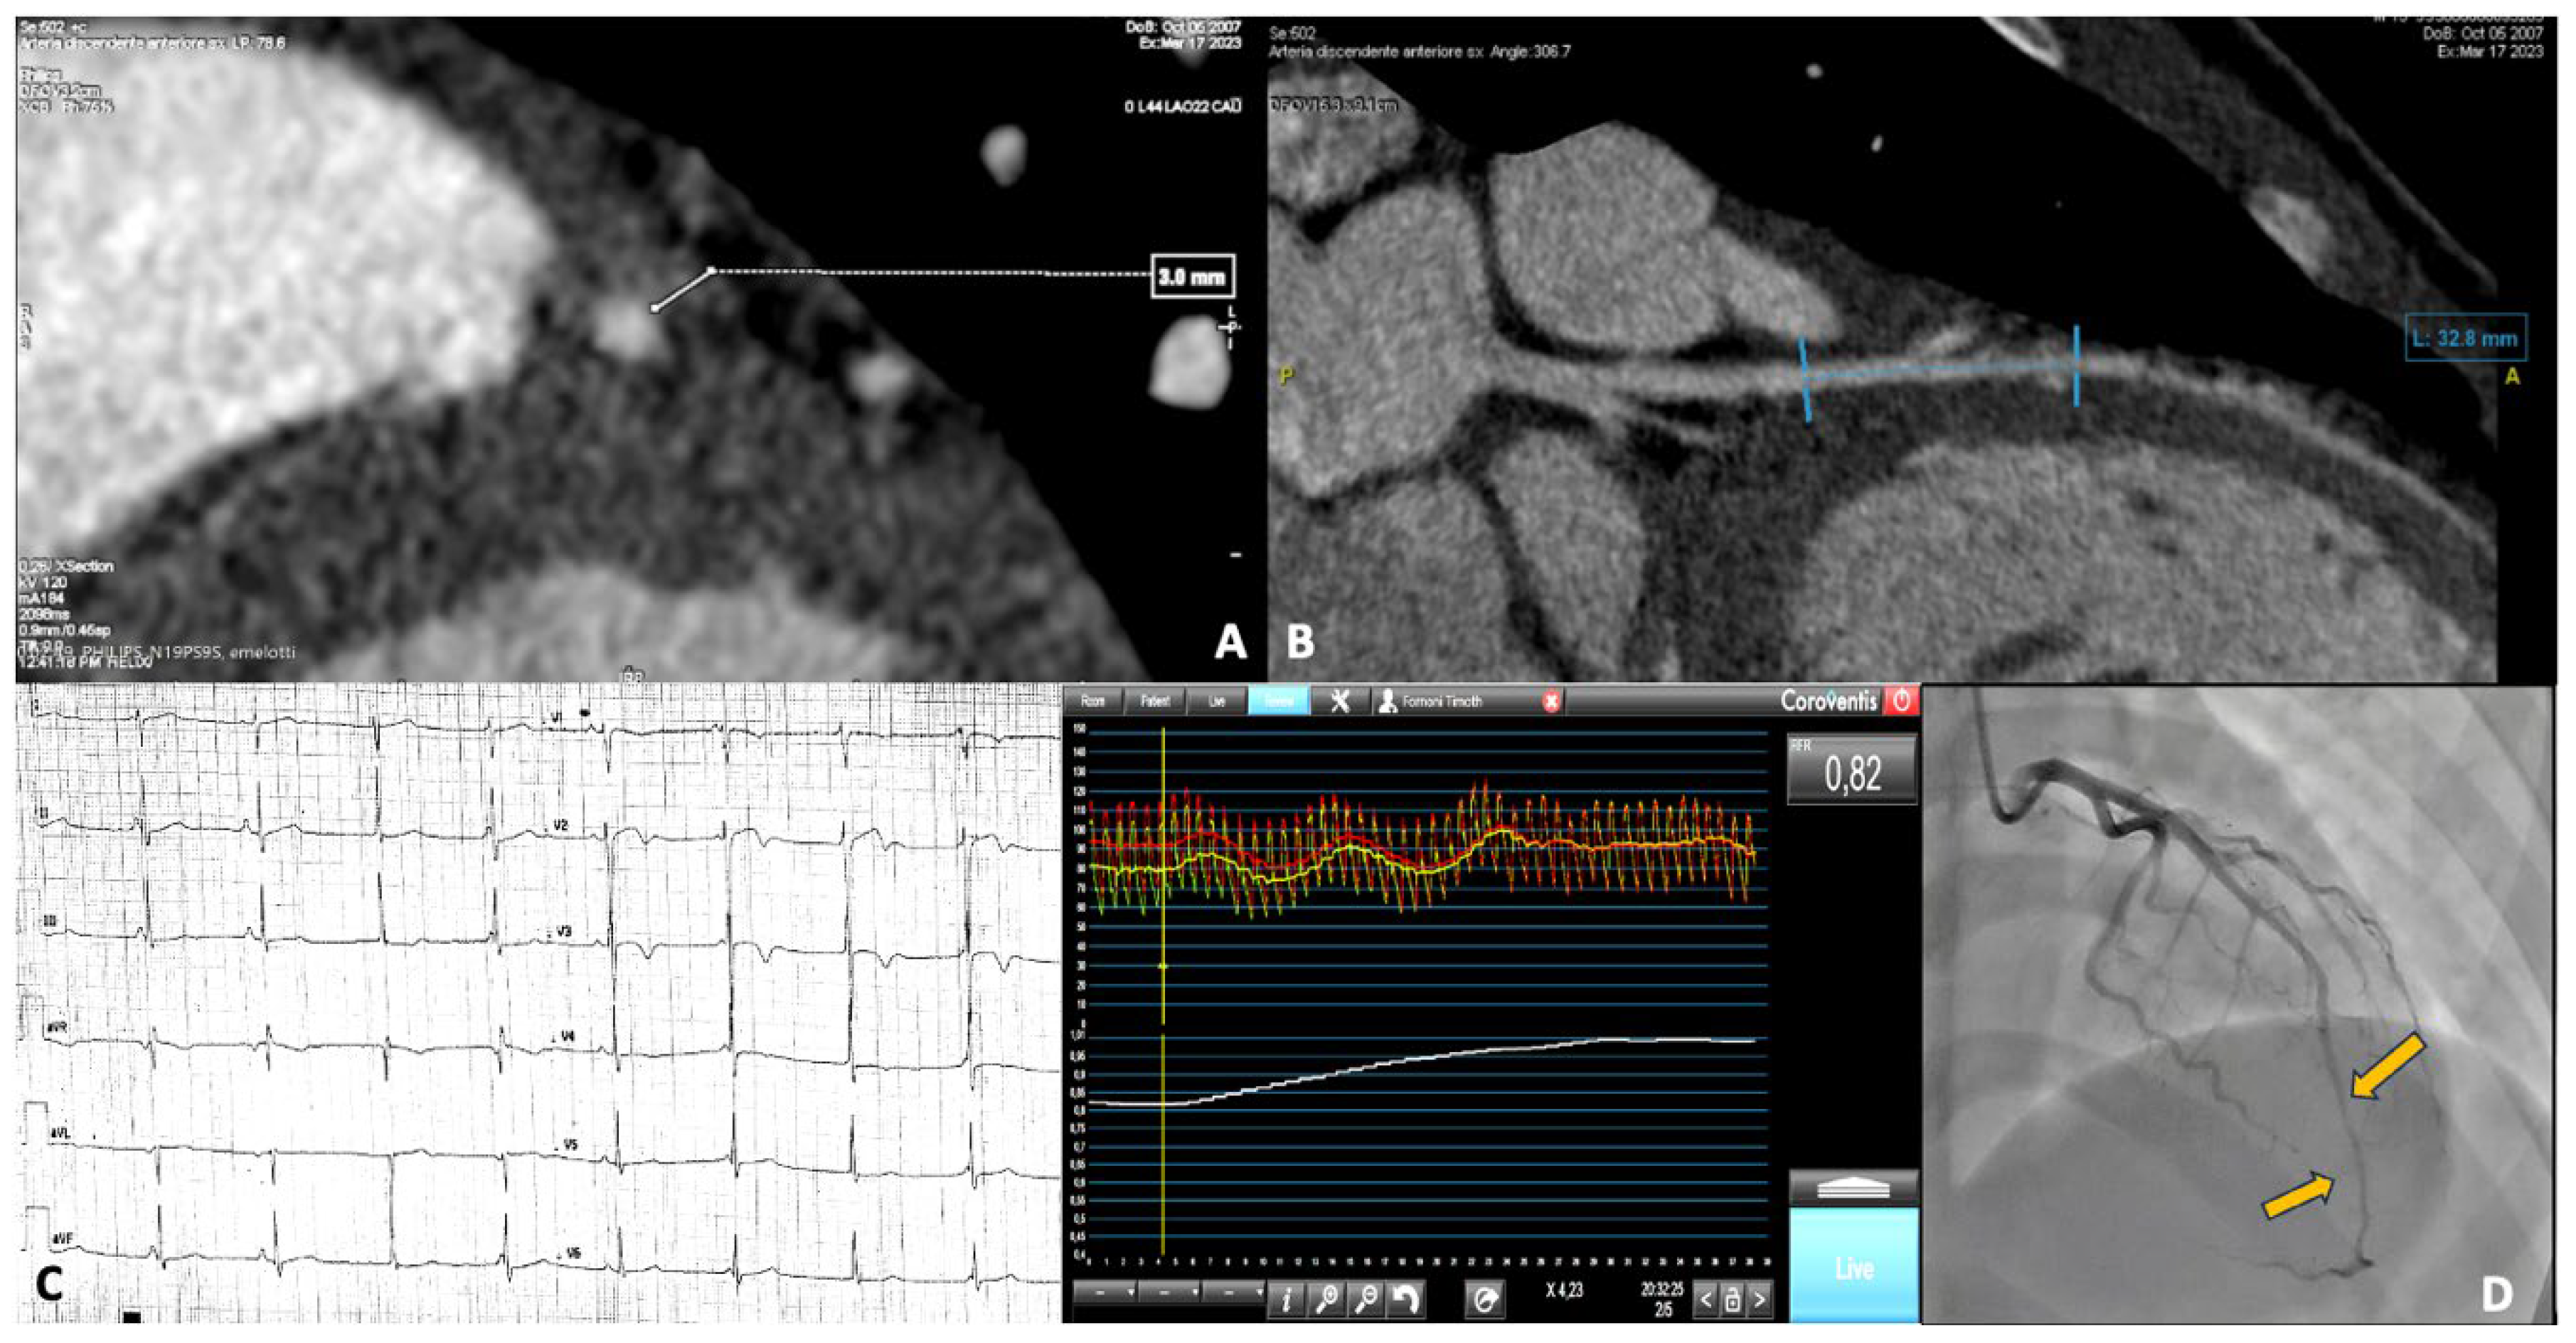

A 15-year-old male, competitive soccer player, presented to the emergency department with chest pain following a soccer match. He was diagnosed with NSTEMI, showing anterolateral repolarization abnormalities with flat T waves and elevated cardiac enzymes. CMR was unremarkable, while coronary angiography revealed the presence of a myocardial bridge involving the mid LAD artery. A subsequent CCTA confirmed a severe myocardial bridge, measuring 30 mm in length and 3 mm in depth. All the investigations on this patient are shown in Figure 2. Panels A and B show the images from the CCTA. Panel C displays the repolarization changes observed on the electrocardiogram (ECG). Panel D presents the myocardial bridge as seen during coronary angiography, along with functional assessment findings.

Figure 2. In panels A and B, the CCTA images show the malignant features of the myocardial bridge, with a length > 25 mm and a depth > 2 mm. In panel C, the anterolateral repolarization abnormalities present at baseline, before correction, are displayed. In panel D, the coronary angiographic study shows the presence of the bridge at the mid-distal LAD, along with the functional assessment, with an RFR value of 0.82.